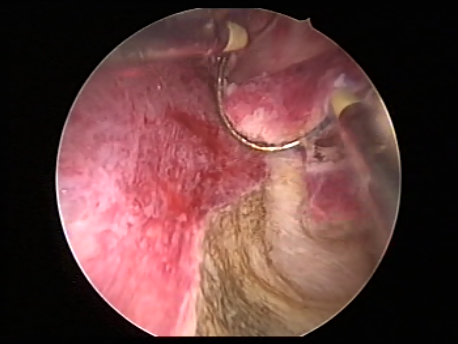

- Intrauterine foreign bodies: Missing copper T embedded in the uterine wall or retained fetal bones or pregnancy following a miscarriage can contribute to irregular bleeding, infection or subfertility.